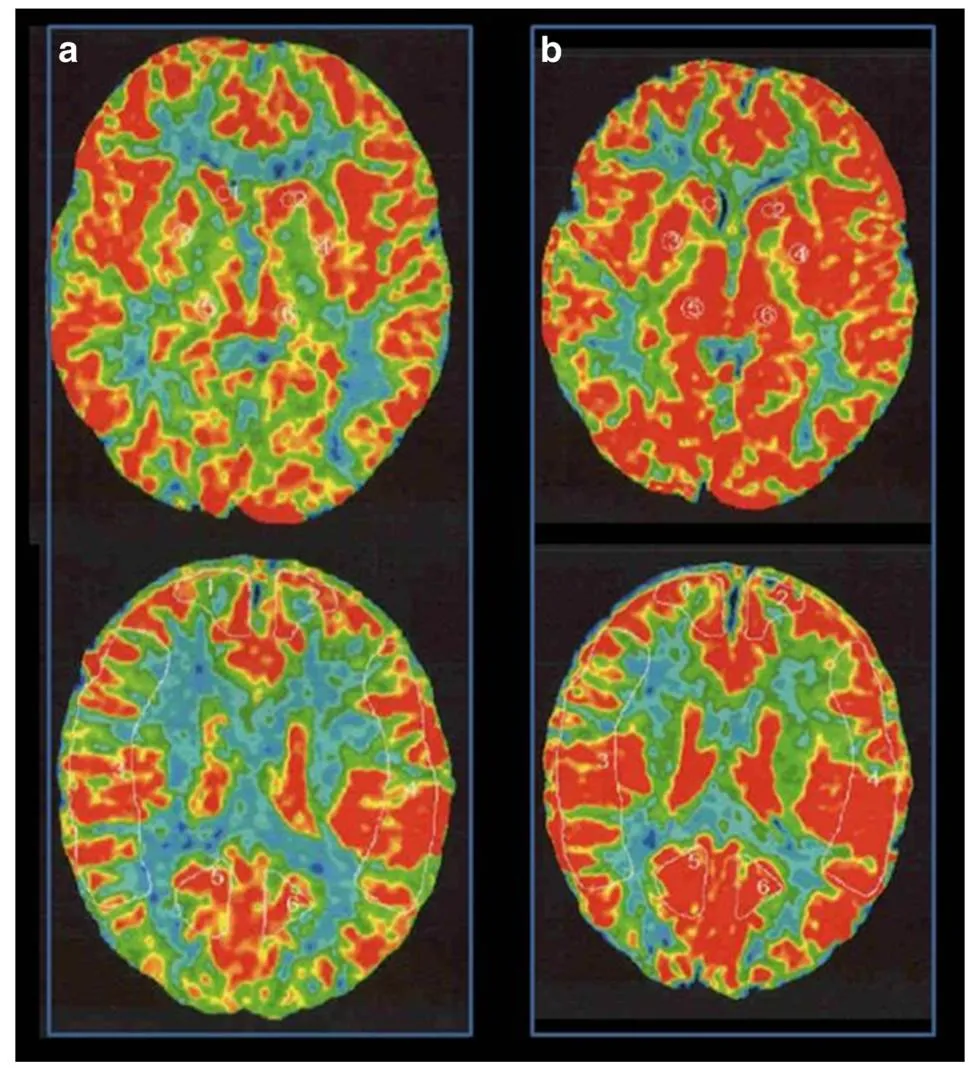

血管造影检查显示右侧颈内动脉末端狭窄,颅内出现典型烟雾状血管,疾病分期为铃木II期(早期),接近III期进展;左侧脑血管未见异常。XeCT(氙气计算机断层扫描)脑血流检查显示静息状态下脑血流量正常,乙酰唑胺激发试验后右侧大脑中动脉供血区脑血管反应性为14.8%。